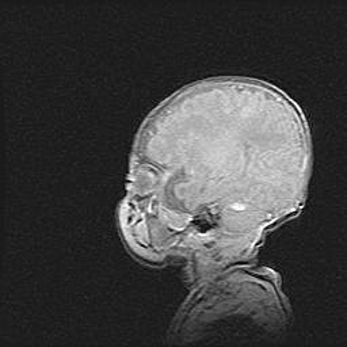

Аномалия Денди-Уокера. Признаки гипоплазии мозолистого тела.

Возраст: 5 месяцев 3 дня

Вес: 5550 г

Пол: мужской

Окружность головы: 39 см

Срок гестации: 40 недель

Аномалия Денди-Уокера – это порок развития головного мозга, для которого характерна триада симптомов: гипотрофия или аплазия червя мозжечка и/или полушарий мозжечка, расширение четвёртого желудочка с формированием ликворной кисты задней черепной ямки, гипертензионная гидроцефалия различной степени.

Гипоплазия мозолистого тела относится к дефектам внутриутробного этапа развития мозговой ткани, возникающим в процессе закладки структур головного мозга, что происходит на начальных этапах развития эмбриона.